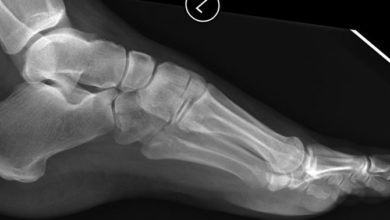

Topuk kemiği kırığı (kalkaneus kırıkları)

En sık kırılan ayak kemiğidir Kırıklar eklem içi ve eklem dışı olarak gruplanır. Sıklıkla yüksekten düşme sonucu gözlenirler. Prof. Dr. Mustafa…